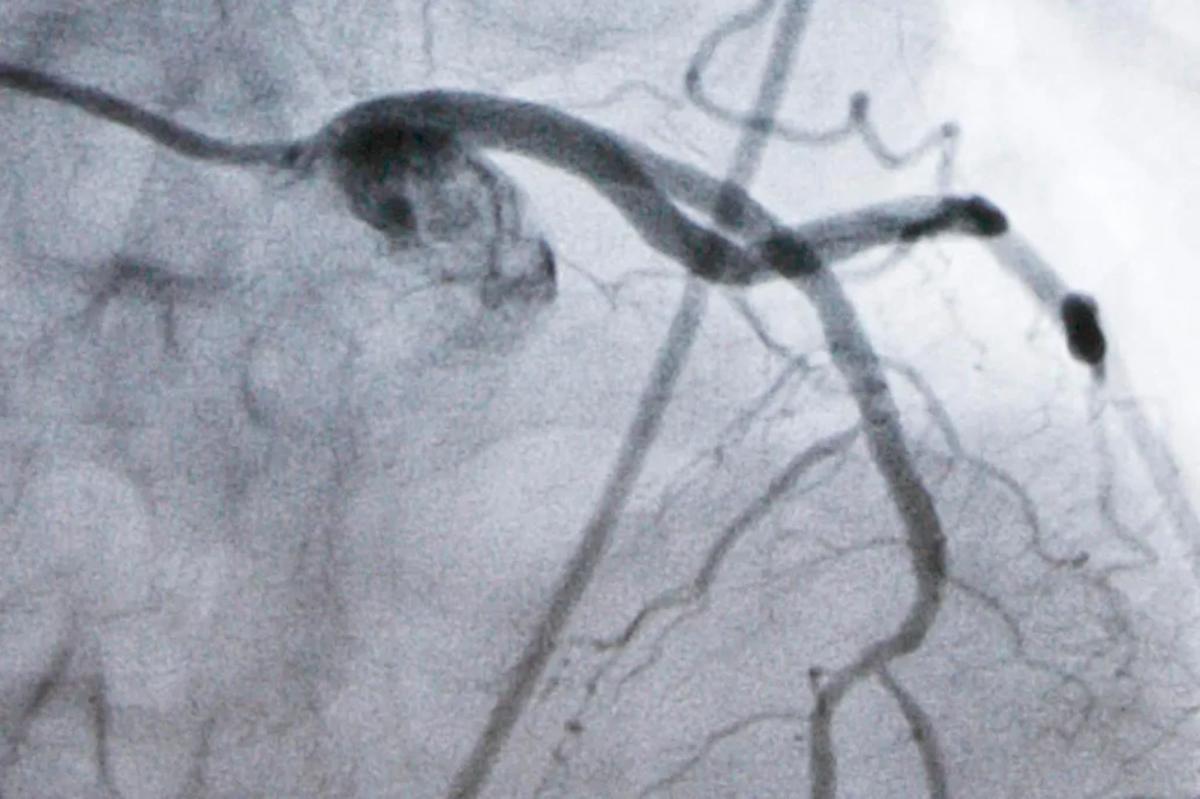

Um monitor mostrando uma artéria durante um procedimento cardíaco em laboratório de cateterismo.